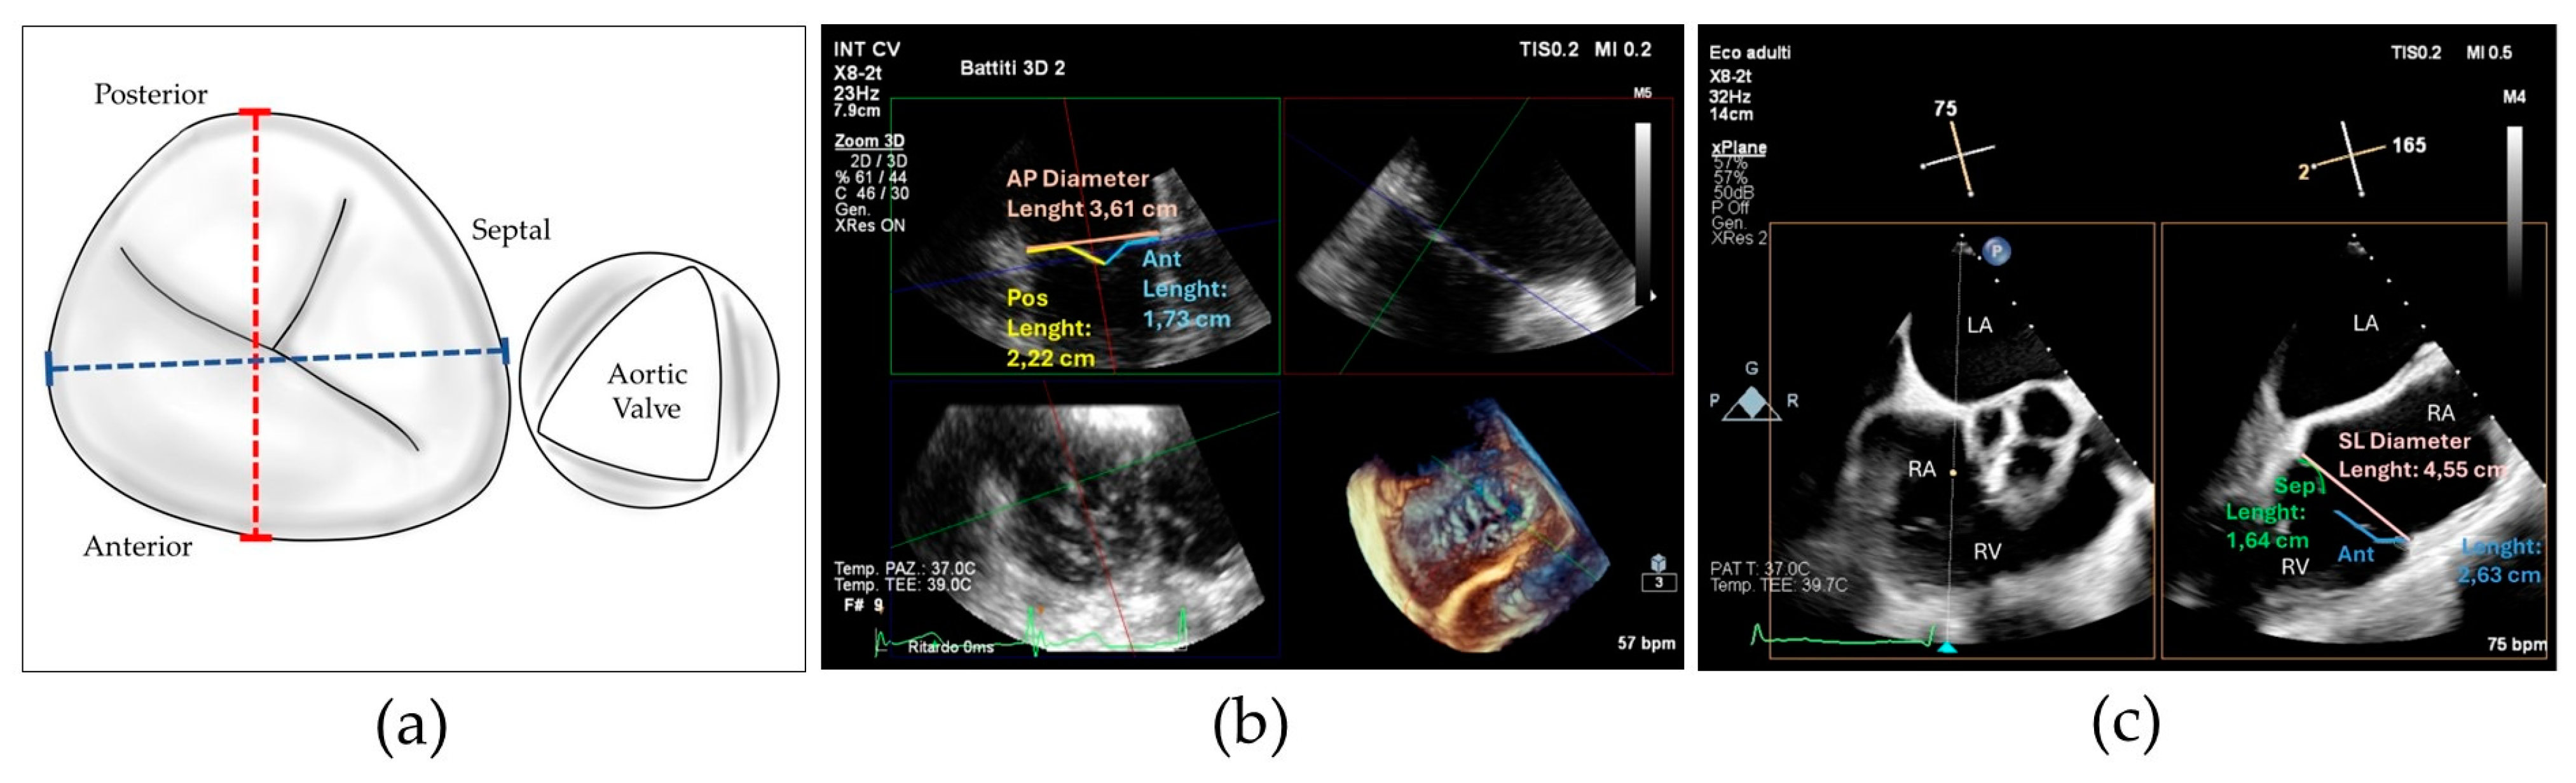

To better characterize this last concept, we collected the prevalence of posterior grasping needed in our population. Jet localizations were divided in 4 categories: isolated central when the prevalent jet was central, isolated antero-septal (AS) when the prevalent jet was located between anterior and septal leaflets, central + AS when both components coexisted and neither one was prevalent on the other, and finally, we included in a last category named as “complex” all the jet localizations which cannot be included in the others, encompassing regurgitation characterized by multiple jets located in the posterior commissures and star-shaped jets (see Figure 2).

We believe that our results can be particularly useful in planning the interventional procedure, especially in patients with complex tricuspid valve anatomies, who may require posterior grasping to optimize procedural outcomes (see Figure 5).

Figure 2. (a) 2D transesophageal echocardiographic transgastric view showing complex tricuspid regurgitation; (b) 2D transesophageal echocardiographic transgastric view showing central + anterior–septal tricuspid regurgitation; (c) drawing showing residual tricuspid regurgitation between anterior and posterior leaflets after implantation of a single clip grasping anterior and septal leaflet.

Figure 5. (a) Transesophageal echocardiographic in the 3D zoom modality showing complex tricuspid valve morphology; (b) the same valve after repair with implantation of three devices individuated by asterisks.